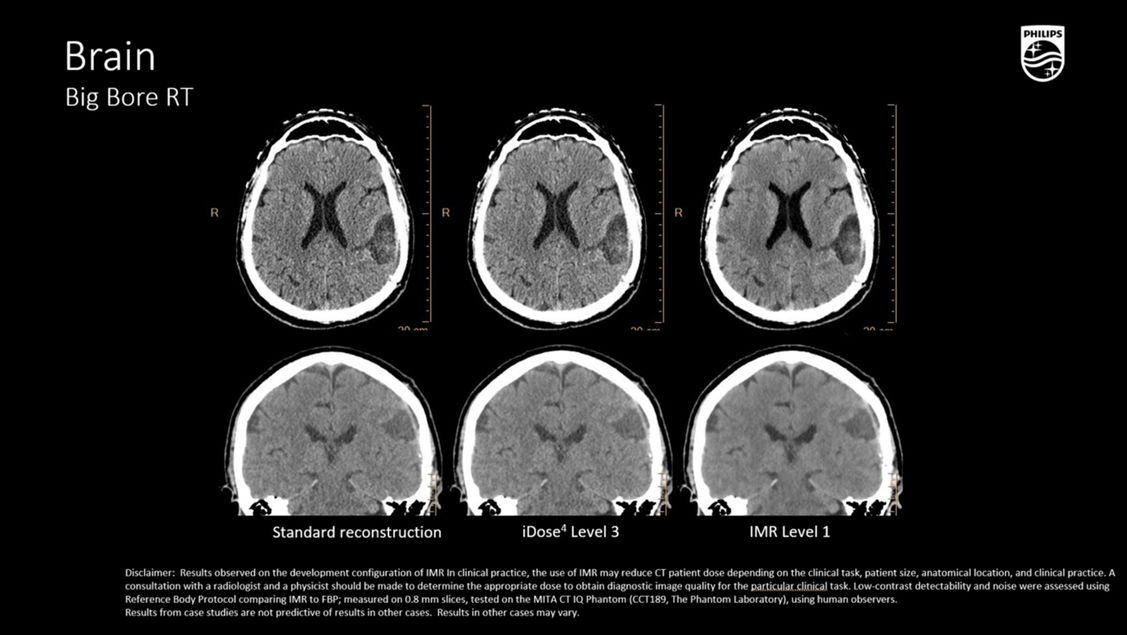

Технология Philips IMR позволяет одновременно снизить лучевую нагрузку на 60—80%, улучшить низкоконтрастное разрешение на 43—80% и снизить шум на 70—83%*. IMR дает уверенность в правильности показателей благодаря улучшенной визуализации мелких деталей